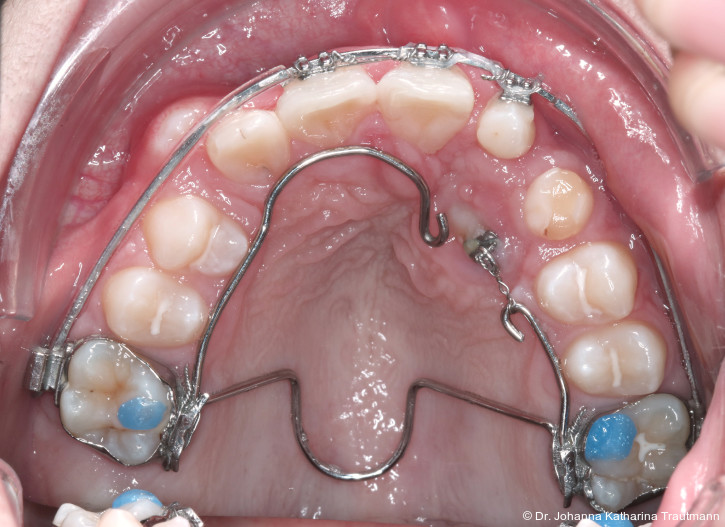

Nach transversaler Nachentwicklung der Maxilla mittels GNE nach Veltri wurde der Zahn 23 geschlossen freigelegt und an einem individualisier ten TPA nach distal angebunden. Zur Aufrichtung der Front und Mesialisierung des hypoplastischen Zahnes 22 kam zusätzlich eine 2x3Mechanik zum Einsatz. Eine rein translatorische Bewegung eines Zahnes ist auch mit einer festsitzenden Apparatur schwer zu erreichen, da der Kraftansatzpunkt nicht identisch mit dem Widerstandszentrum des Zahnes ist.7 Diese Problematik kann einerseits durch das Einbringen eines Versetzungsmomentes adressiert werden, andererseits durch eine Verlagerung des Kraftansatzpunktes. Angelehnt an den von Hong et al. beschriebenen Power Arm 8 wurde hierfür palatinal an Zahn 22 ein cranial gerichteter Hook angebracht (Abb. 3). Da Zahn 22 aufgrund seiner Hypoplasie eine verkürzte Wurzel aufwies, konnte so die Distanz zwischen Widerstandszentrum und Kraftangriffspunkt effizient reduziert werden. Eine weitere biomechanische Schwierigkeit stellte das geringe Alveolarknochenangebot im Spalt bereich mesial von 22 dar. In Bereichen mit Knochendefizit verschiebt sich das Widerstandszentrum nach apikal und wie in diesem Fall zusätzlich nach distal.9, 10 Um dem erhöhten Risiko für Kipp bewegungen entgegenzuwirken, muss hier besonders auf die Steuerung des M/F-Quotienten geachtet werden. Der vestibulär durchgebrochene Zahn 13 benötigte keine Freilegung. Um seine korrekte Einstellung zu ermöglichen, wurde die Mesialwanderung des Zahnes 16 mithilfe des TPAs korrigiert sowie eine Mittellinienkorrektur nach links mittels 2x3 Mechanik durchgeführt.